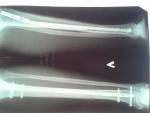

Здравствуйте, 9.12.2015 я умудрился сломать большеберцовую и малоберцовую кости левой ноги. 14.12.2015 произведена операция (закрытый блокируемый интрамедуллярный остеосинтез большеберцовой кости). Боли беспокоили первых две недели. Через 7 недель сделали контрольный снимок и разрешили передвигаться с одним костылем (50-70%) нагрузки на травмированную ногу. Первых пару дней только радость и страх сильно наступить. Беспокоили только легкие боли в суставах ноги, место перелома не тревожило вовсе. Сегодня проснулся с ощущением что нога ПОЛОМАНА. Появилась боль и небольшая припухлость в месте перелома. При легкой пальпации места перелома ощущается местная температура и болевой отклик.

Снимок контрольный. После операционного к сожалению у меня нет дома.

Возможны ли нагрузка на ногу при такой стадии срастания костей? Характерны ли такие симптомы при начале нагрузок? Или я все токи просто переусердствовал.

Очевидно, Вы переусердствовали с нагрузкой. Стоит дать ноге покой на пару дней. Если это не поможет - обратитесь к врачу